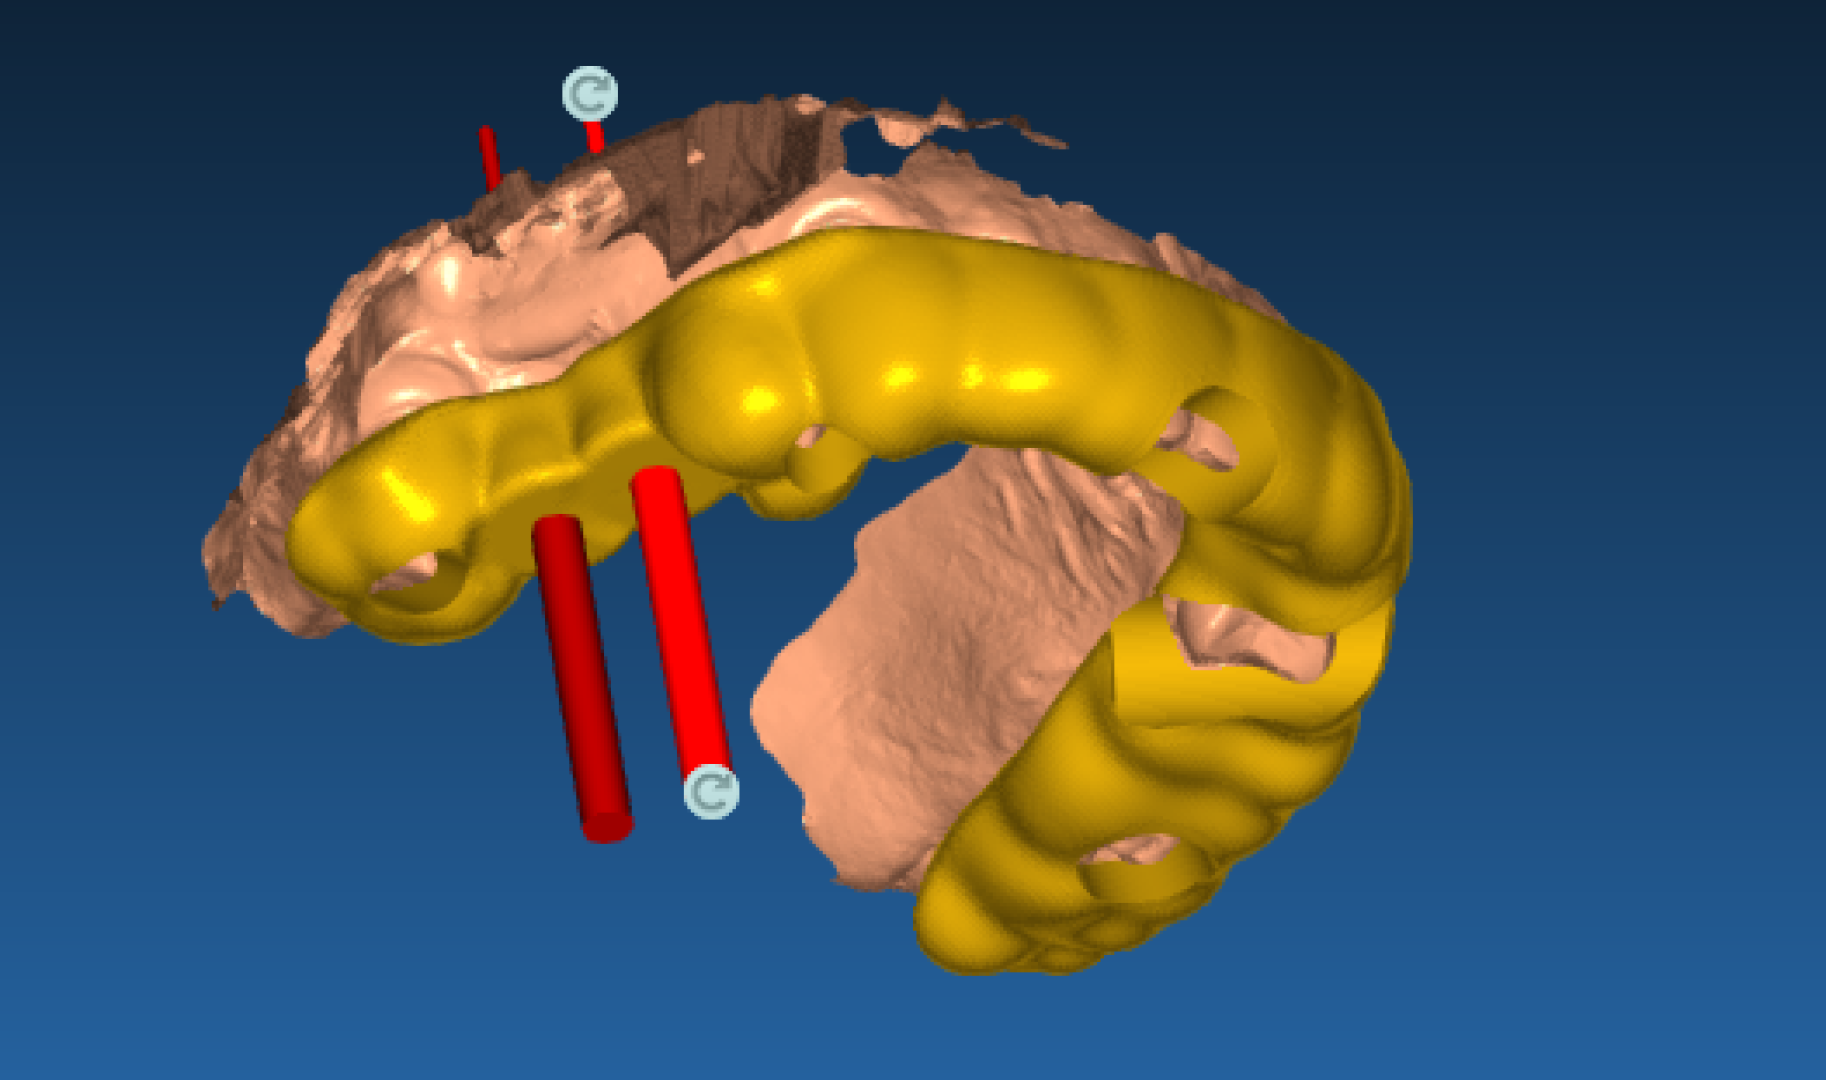

Хирургический 3D-шаблон для имплантации: планирование установки имплантов

Необходимость восстановления отсутствующих зубов с помощью имплантации. Требовалось максимально точное и безопасное позиционирование имплантов в костной ткани для долгосрочного прогноза и эстетики.